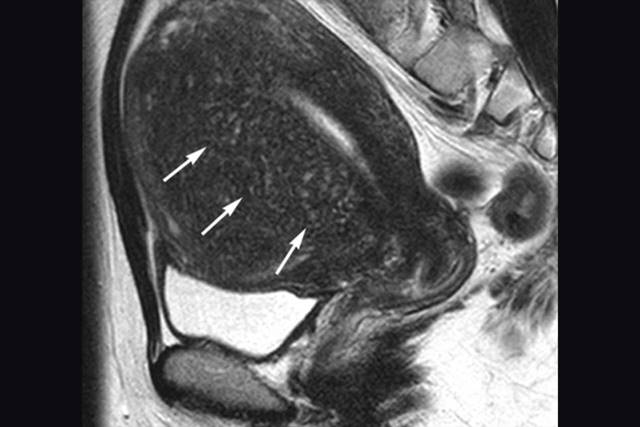

Adenomyosis

Adenomyosis is one of the disease spectra or variants of endometriosis. It is called adenomyosis when the endometrium tissue infiltrates the uterus’s muscle layer, causing muscle breakdown, fibrosis formation, and an island of blood cysts within a confined area of the uterus or it might even affect the entire uterus. It causes severe menstrual cramps, heavy and prolonged menstrual bleeding, and even infertility.

Though adenomyosis is considered a benign (not life-threatening) condition, the frequent pain and heavy bleeding associated with it can have a negative impact on a woman’s quality of life. Adenomyosis is a common condition and most often diagnosed in middle-aged women and women who have already had children.